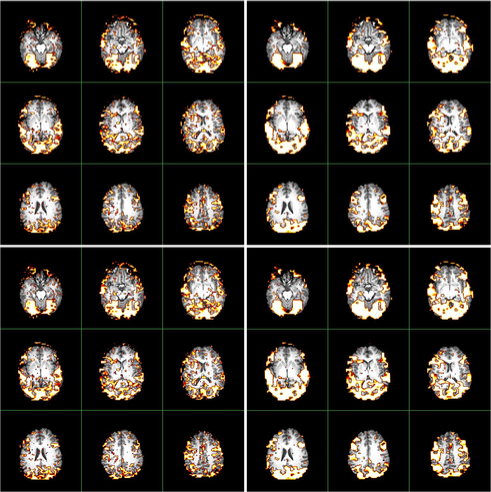

We apply the and procedures to detect activated brain regions of a simulated brain fMRI dataset, which is both spatially and temporally correlated. The experiment design, timings and size are exactly the same as those of the real fMRI dataset in Section 7.

The data are generated from a semi-parametric model similar to that in Section 5.2 of Zhang and Yu (2008). (They demonstrated that the semi-parametric model gains more flexibilities than existing parametric models.) The left panel of Figure 6 contains slices (corresponding to the 2D axial view) which highlight two activated brain regions involving activated brain voxels. The neighborhood used in the procedure is illustrated in the right panel of Figure 6.

Figure 7 compares the activated brain regions identified by the (in the left panels) and (in the right panels) procedures. Owing to the wealth of data, and for purposes of computational simplicity, results using Method I of are presented. Voxel-wise inactivity is tested with the semi-parametric test statistics (in the top panels) and (in the bottom panels) whose notation was given and asymptotic distributions were derived in Zhang and Yu (2008). The control level is . Inspection of Figure 7 reveals that and locate both active regions. In particular, using the procedure, both methods detect more than voxels (which are visible when zooming the images), many of which are falsely discovered. When applying the procedure, detects voxels, whereas detects voxels. Thus the procedure reduces the number of tiny scattered false findings, gaining more accurate detections than the procedure.

A comparison of the activated brain regions using the and procedures is visualized in Figure 9. The level is used to carry out the multiple comparisons. The conventional procedure finds more tiny scattered active voxels, which are more likely to be falsely discovered. In contrast, the procedure finds activation in much more clustered regions of the brain.